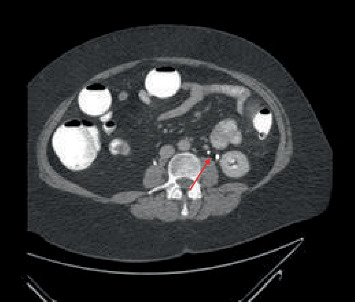

Ureteric duplication is a variation of the urinary tract which can have significant impact in the urologic reconstructive setting. We present the incidental diagnosis and management of a 68-year-old man who was found to have a double ureter in the context of a radical cystectomy.